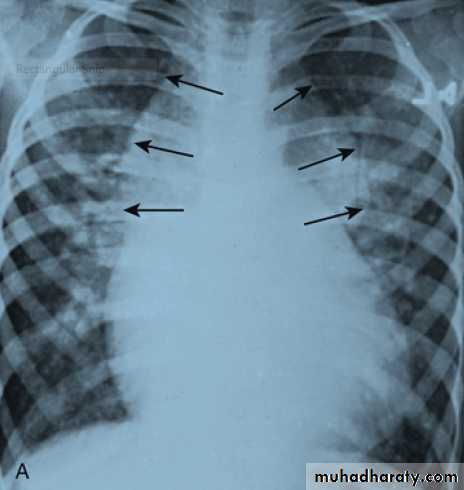

• Cardiomegaly, rib notching on X-ray.• ECG in older children may be normal or may show LVH.

Notching of the ribs caused by marked enlargement

of the intercostal collaterals .